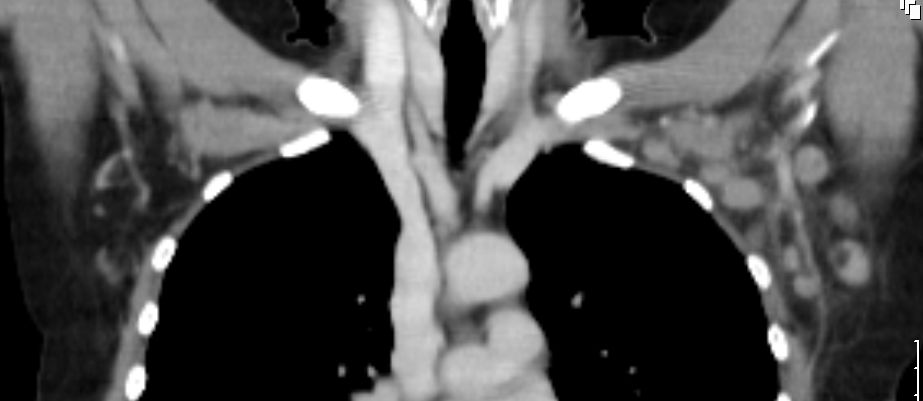

Koronares CT mit Darstellung zahlreicher

Lymphknotenmetastasen links axillär

52-jährige Frau, bei der vor einem Jahr ein 15 mm großes invasiv-duktales Mammakarzinom rechts o/iq nach 3 Wochen Letrezol (Adapt-Studie) operiert wurde. Postoperativ ypT1c, ypN0 (0/2 sn), cM0, L1 V0 R0, G2, ER: 6/12, PR: 0/12, HER-2/neu: negativ, Ki-67: 30%, Oncotype DX Recurrence Score 40. CHT: 8 x nabPaclitaxel -> 4 x EC. Dann Bestrahlung der Brust. AHT mit Letrozol. Jetzt palpable Lymphknotenmetastasen supraklavikulär rechts. CT: Die teilweise rechts retroklavikulär hinter der rechten medialen Klavikula und supraklavikulär gelegenen Lymphknotenmetastase hat eine Größe von maximal 2,5 cm. Weiter oberhalb und dorsalseitig sind im rechten unteren Halsdreieck dorsal der rechten Vena jugularis externa konfluierende inhomogene Lymphknoten mit Einzelgrößen bis zu 1,5 cm und einer Gesamtpaketausdehnung bis zu 4 cm sichtbar. | ||